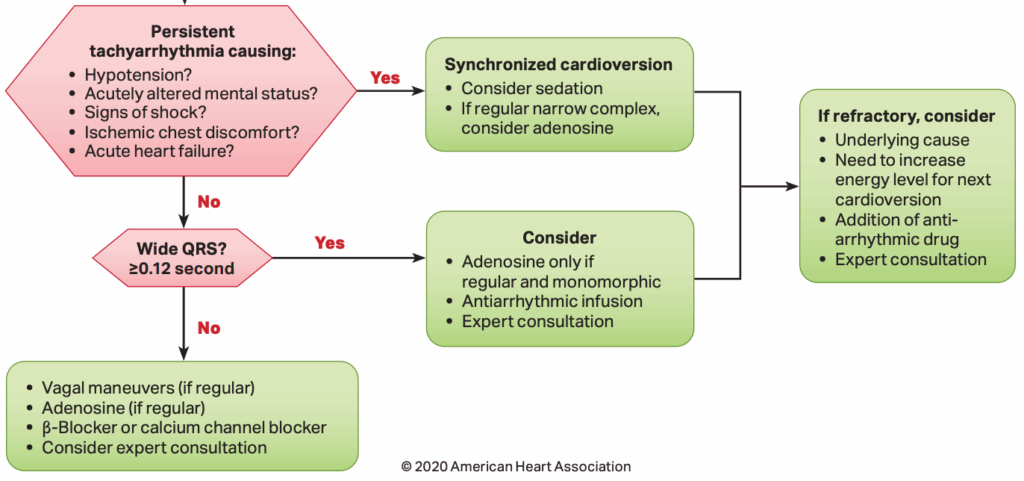

Y, ahora, ¿qué hacemos? Pues dar manejo a la taquiarritmia inestable (ventanas clínicas de hipoperfusión tisular positivas en esta mujer). Veamos puntos clave recomendados en el Algoritmo de Taquicardia con Pulso2 del manual ACLS vigente al día de hoy:

En nuestra paciente la taquiarritmia generó alteración del estado mental y tiempo de llenado capilar distal, por lo cual realizar una cardioversión sincronizada estaba indicado. ¿Qué pasó después? Eso lo dejaremos para otra ocasión.